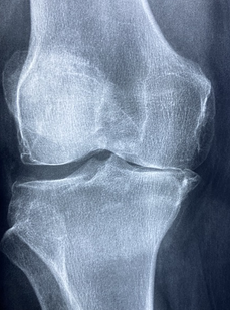

무릎 염증 증상에 대해 알아보겠습니다. 무릎 염증은 무릎 관절이나 주변 조직에 염증 반응이 일어나는 상태를 말합니다. 염증 반응은 신체가 손상이나 자극을 치유하려고 할 때 일어나는 자연적인 과정입니다. 그러나 염증이 지속되거나 과도하면 통증, 부종, 뻣뻣함 등의 증상을 유발하고 관절 기능을 저하시킬 수 있습니다.

무릎 염증의 증상은 다음과 같습니다.

- 무릎 통증: 무릎을 움직일 때, 걷거나 서있을 때, 비가 오거나 날씨가 변할 때 통증이 심해집니다.

- 무릎 부종: 무릎 부위가 붓고 따끔하게 느껴집니다.

- 무릎 뻣뻣함: 무릎을 구부리거나 펴기 어렵고, 오래 앉아 있거나 자다 일어날 때 더 심해집니다.

- 무릎 소리: 무릎을 움직일 때 삐걱거리는 소리가 납니다.

- 무릎 변형: 무릎 모양이 비정상적으로 바뀌거나, 안정성이 떨어집니다.